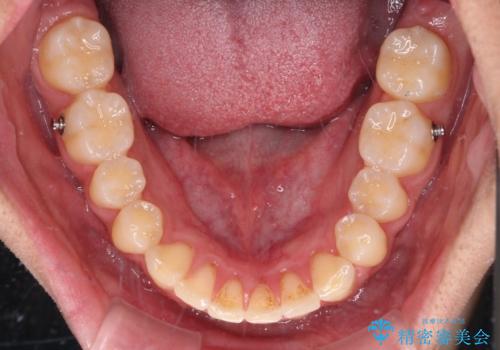

- 上下前歯のデコボコと、それに伴う出っ歯を気にして来院された患者様です。

インビザラインによる上下歯列の側方拡大と後方移動、IPR(歯と歯の間を削る)にるスペースの獲得により歯列を整えることとしました。

歯と歯の間を削ることでうまくスペースコントロールでき、また、毎日22時間以上しっかりとマウスピースを装着していただいたので、スムーズに治療が進みました。